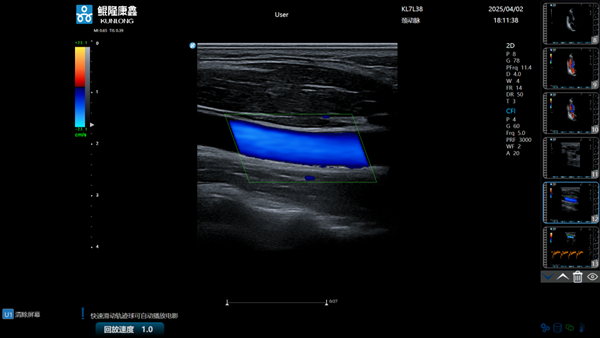

克日,,,在包河区中国视界园区,,,安徽鲲隆康鑫医疗科技有限公司(简称“鲲隆康鑫”)生产的“彩色多普勒超声诊断仪”正式获批量产,,,这是安徽本土企业自主研爆发产的首款彩色超声影像诊断装备,,,标记着安徽省在高性能医学影像装备领域实现重大突破。。

据悉,,,鲲隆康鑫自主研发的彩色多普勒超声诊断仪是一款集成了先进超声成像手艺的立异型医疗装备,,,该产品依附128通道数字波束形成手艺,,,实现黑点追踪、组织多普勒成像等多种高级成像功效,,,具有图像清晰、功效周全、操作便捷等特点,,,在要害手艺指标上已靠近国际主流水平,,,可用于腹部、心脏、血管、妇产等临床诊断,,,为临床医生提供更精准、更高效的诊断依据。。